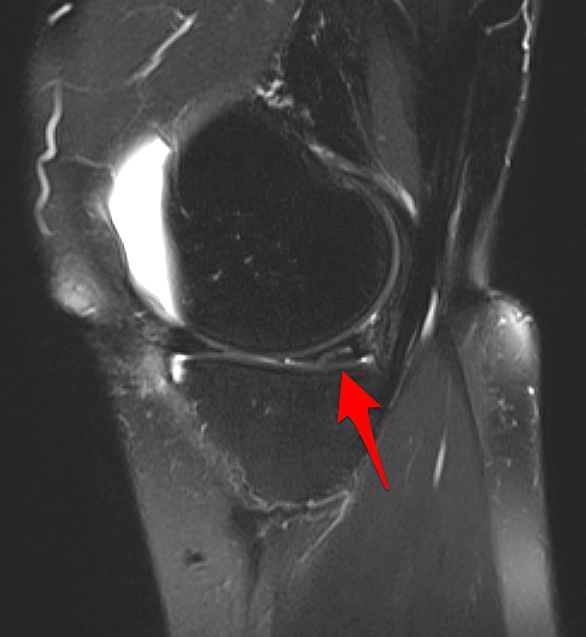

One of the most common knee MRI diagnoses - and a finding well worth being familiar with, even if you're not a Radiologist. An oblique meniscal tear of the posterior horn. #orthotwitter